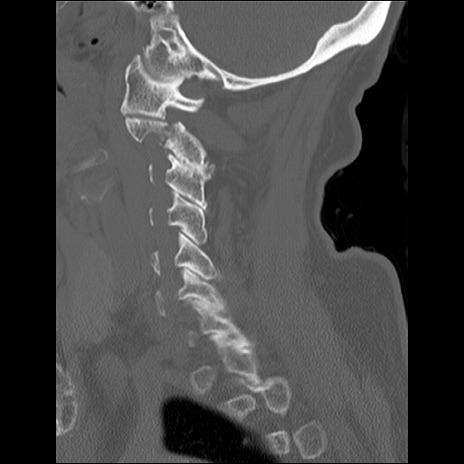

症例48 頚椎CT(矢状断像)

頚椎CT